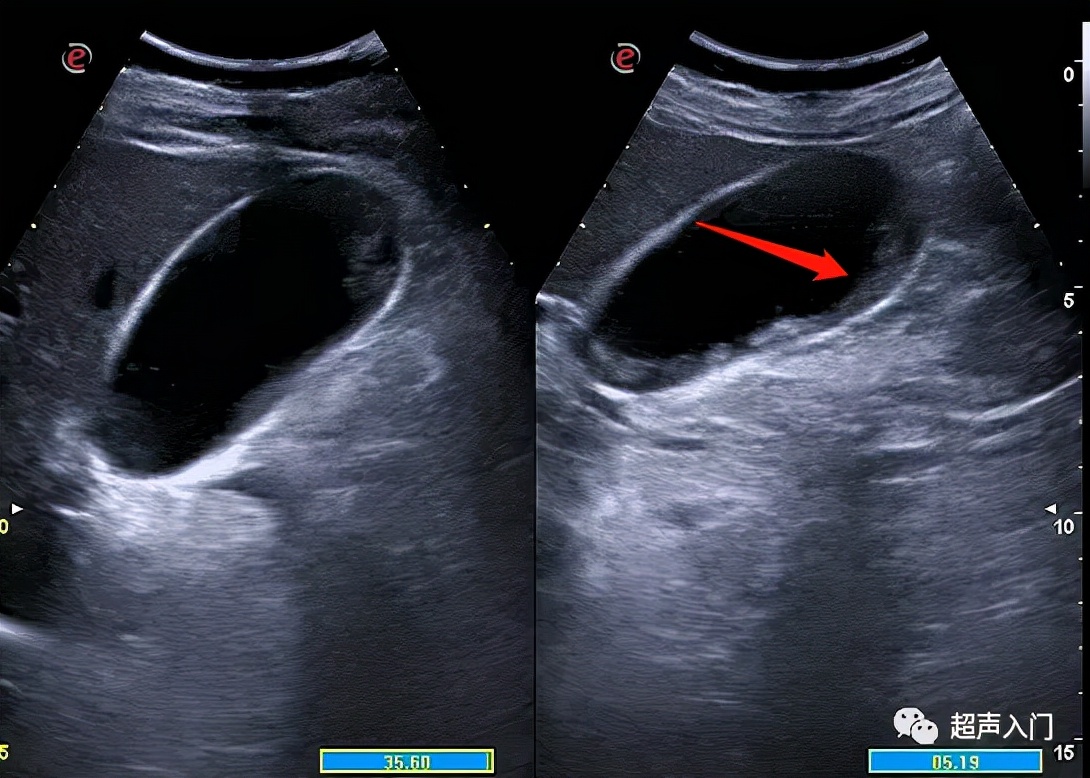

但常规超声往往很难对其进行准确分类,囊内透声好并不代表没有化脓,如上图,囊内透声很好,但患者持续发热,胆囊置管后,抽出脓性胆汁。

脓性胆汁

3、胆囊切面无回声区内出现稀疏或密集的分布不均的细小或粗大回声斑点,呈云雾状,为胆囊积脓的表现。